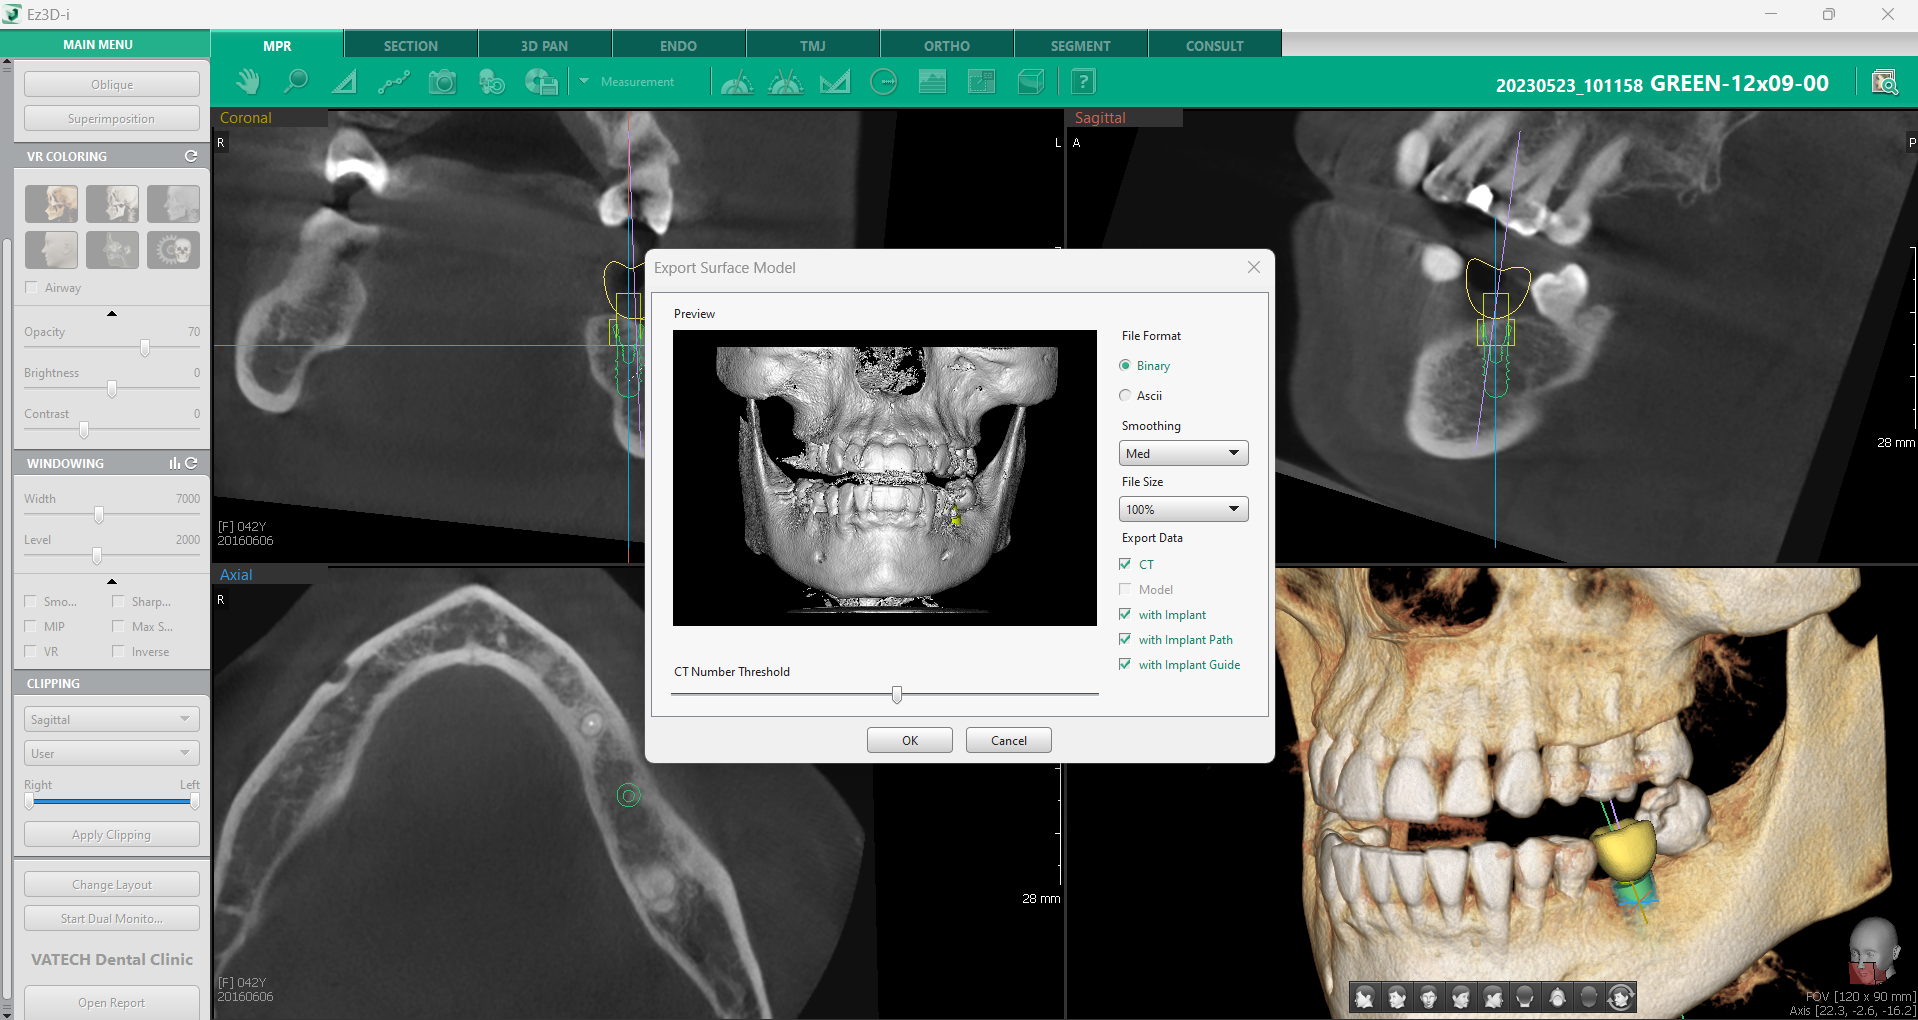

5. Ajustări și pregătirea implantului pentru CAD/CAM

După ce implantul a fost plasat și poziționat corect, urmează etapa finală de ajustare și pregătire pentru integrarea cu sistemele CAD/CAM. Această etapă este esențială pentru a obține o restaurare precisă și adaptată perfect pacientului.

Software-ul Ez3D-i oferă multiple opțiuni pentru ajustarea fină a implantului, permițând modificarea poziției, dimensiunea și orientarea acestuia în funcție de necesitățile clinice. Pentru o precizie maximă, se poate utiliza controller-ul virtual, un instrument care permite modificări detaliate asupra poziției implantului. Există două tipuri de controllere – unul dedicat implantului în sine și altul destinat coroanei. Accesarea acestora se face simplu, printr-un click dreapta pe componenta dorită și selectarea opțiunii „Afișare controller”.

În cazul în care dimensiunea inițială a implantului nu corespunde perfect cu anatomia pacientului, software-ul oferă și opțiunea de redimensionare. Prin click dreapta pe implant și selectarea opțiunii “Edit implant”, se poate ajusta lungimea, dimensiunea ocluzală și dimensiunea apicală. Modificările sunt aplicate automat, în conformitate cu linia de implant aleasă.

Odată ce toate ajustările au fost realizate, urmează exportarea modelului pentru integrarea cu sistemele CAD/CAM. Aceasta se face rapid, accesând meniul principal și selectând “Export Surface Model”. Caseta de dialog ghidează întregul proces, oferind opțiuni pentru formatul fișierului, nivelul de netezire, dimensiunea și tipul de date care urmează să fie exportate.

Această etapă finală asigură o restaurare dentară precisă și un rezultat predictibil, optimizând fluxul de lucru în cabinetul stomatologic și îmbunătățind experiența pacientului.